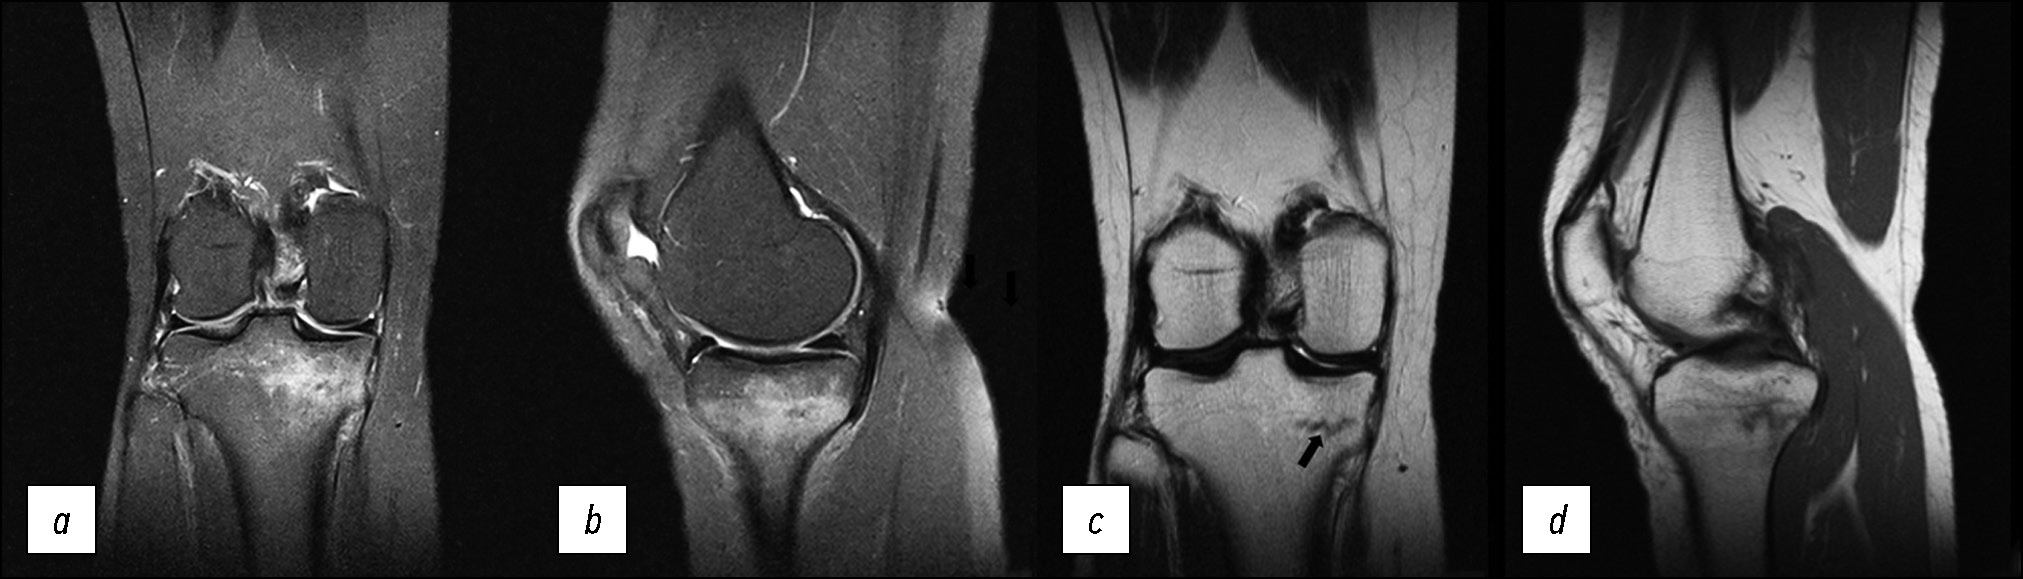

Пациентка В., 60 лет, обратилась с болью в левом коленном суставе, которая беспокоит её в течение нескольких лет. На МР-томограммах (рис. 7) выявлен равномерный отёк костного мозга в области внутреннего мыщелка большеберцовой кости.

Рис. 7. МР-томограммы коленного сустава: a, b — корональная и сагиттальная проекции в режиме PD с подавлением сигнала от жировой ткани при III стадии остеоартрита, c — сагиттальная проекция в режиме Т1; d — графическое изображение. Отёкоподобное усиление сигнала костного мозга внутреннего мыщелка левой большеберцовой кости, сочетающееся с истончением или отсутствием хряща, обозначается как остеит.

Fig. 7. MRI scans of the knee: a, b — coronal and sagittal views in to suppress the signal from adipose tissue with an osteoarthritis knee, c — sagittal views in to T1. Graphic image of an osteoarthritis knee (d). Edema-like marrow signal intensity (ELMSI).

Характерными особенностями отёка кости при остеоартрите являются его равномерность, отсутствие горизонтальных линий в субхондральной области и самое важное — значительное истончение или отсутствие гиалинового хряща в области мыщелка, что отличает его от начальных стадий асептического некроза, где гиалиновый хрящ полностью сохранён.

Отёкоподобное усиление сигнала костного мозга в таких случаях обозначается термином «остеит».

Клинический случай 8. Ревматоидный артрит (Rheumatoid arthritis, RA)

Пациент А., 63 года, обратился с жалобами на периодическую боль и отёк в правом коленном суставе в течение нескольких лет. Около 10 лет назад поставлен диагноз «ревматоидный артрит», по поводу чего получает лечение, включая нестероидные противовоспалительные препараты, метотрексат и внутрисуставные инъекции глюкокортикостероидов.

Особенностью отёка костной ткани, выявленного на МР-томограммах (рис. 8), является его локализация. Очаги встречаются как в нагружаемых (мыщелки бедренной и большеберцовой кости), так и в ненагружаемых областях (межмыщелковое возвышение). Нет чёткого отграничения здоровой кости от поражённых участков, что является отличием от вторичного остеонекроза костей, развивающегося, например, на фоне приёма глюкокортикостероидов. В то же время локализация в разных участках бедренной и большеберцовой кости подчёркивает вторичный характер поражения. Структура гиалинового хряща истончена равномерно, и его изменения не зависят от локализации отёка в костной ткани, что отличает отёк при ревматоидном артрите от остеита при деформирующем остеоартрите коленного сустава.

Рис. 8. МР-томограммы коленного сустава: a, b — корональная и сагиттальная проекции в режиме PD FS с подавлением сигнала от жировой ткани при ревматоидном артрите.

Fig. 8. MRI scans of the knee: a, b — coronal and sagittal views in to suppress the signal from adipose tissue with a rheumatoid arthritis.